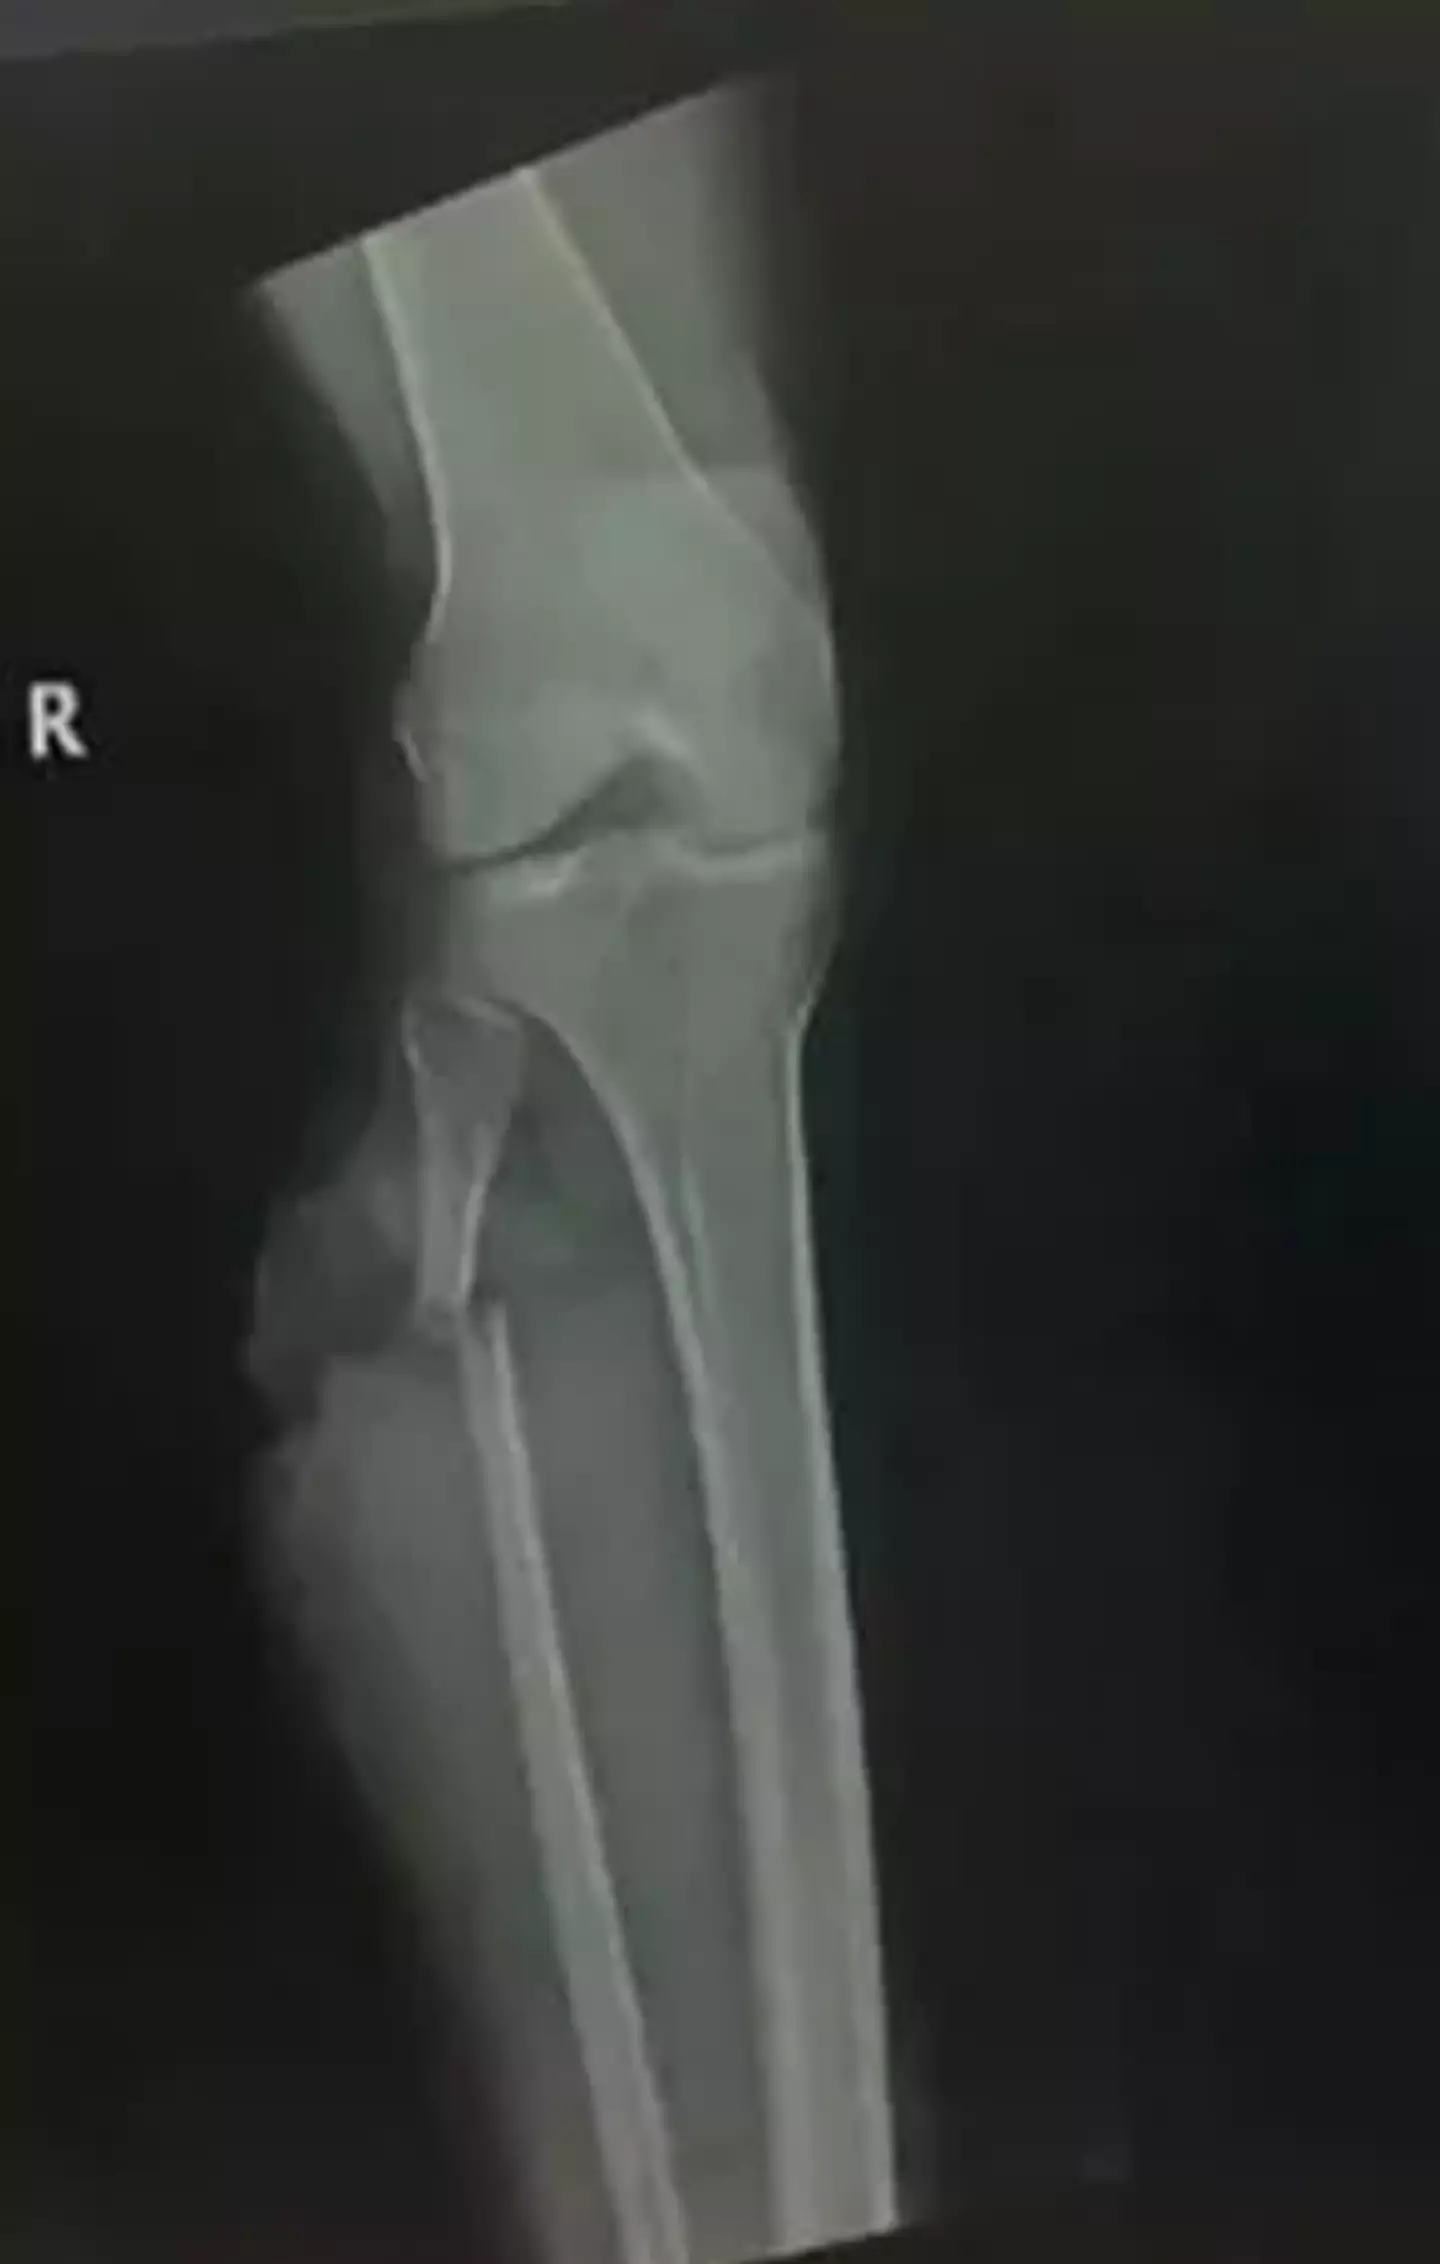

Thompson was later found by a neighbour and her son, who took her to a nearby hospital, with doctors saying that her leg was in a bad condition and could potentially be infected.

To avoid this risk, she underwent surgery on her leg, which is still unfortunately at risk of infection, but she detailed that she feels lucky to still be alive after everything.